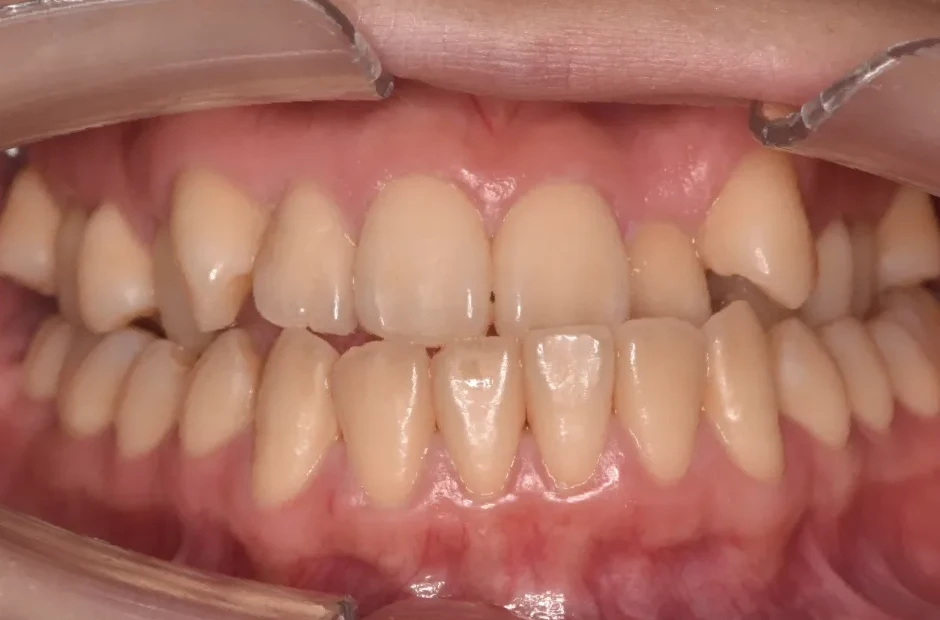

叢生

| 診断名・主訴 | 叢生 |

|---|---|

| 年齢・性別 | 43歳・女性 |

| 治療期間・回数 | 2年7か月 27回 |

| 治療に用いた主な装置 | 舌側矯正 |

| 抜歯部位 | 両顎4,4 |

| 治療費 | 100万円(税抜) |

| リスク・副作用 | 装置による違和感・疼痛・歯肉退縮・歯根吸収・虫歯のリスクなど |

治療前